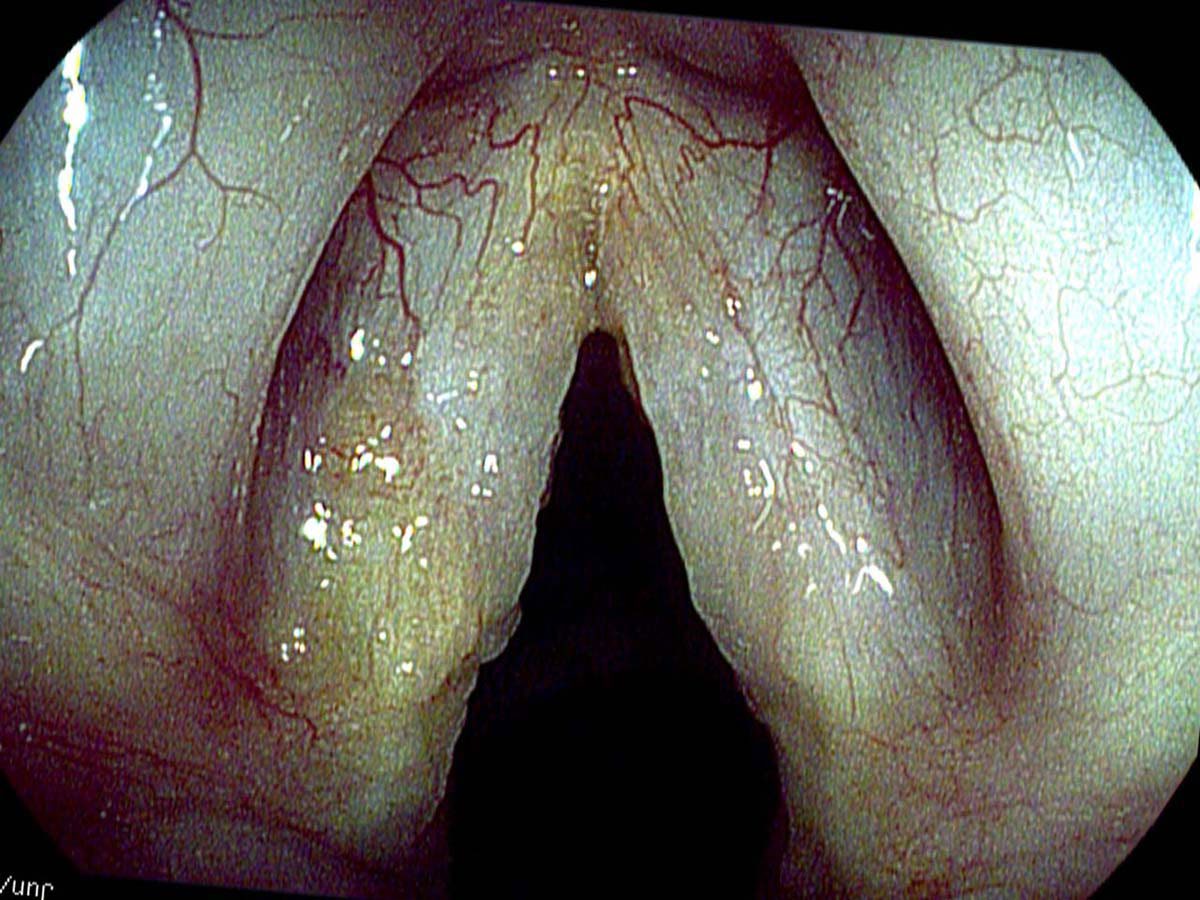

Another type of amyloidosis consists of deposits into the false vocal cords. If the false cords enlarge enough with the deposits, they eventually can put pressure on the true vocal cords and dampen the vibrations. The current treatment is to remove the deposits with surgery — very gentle surgery if the deposits are on the true vocal cord. The deposits will likely gradually reoccur over time. They can be removed again.